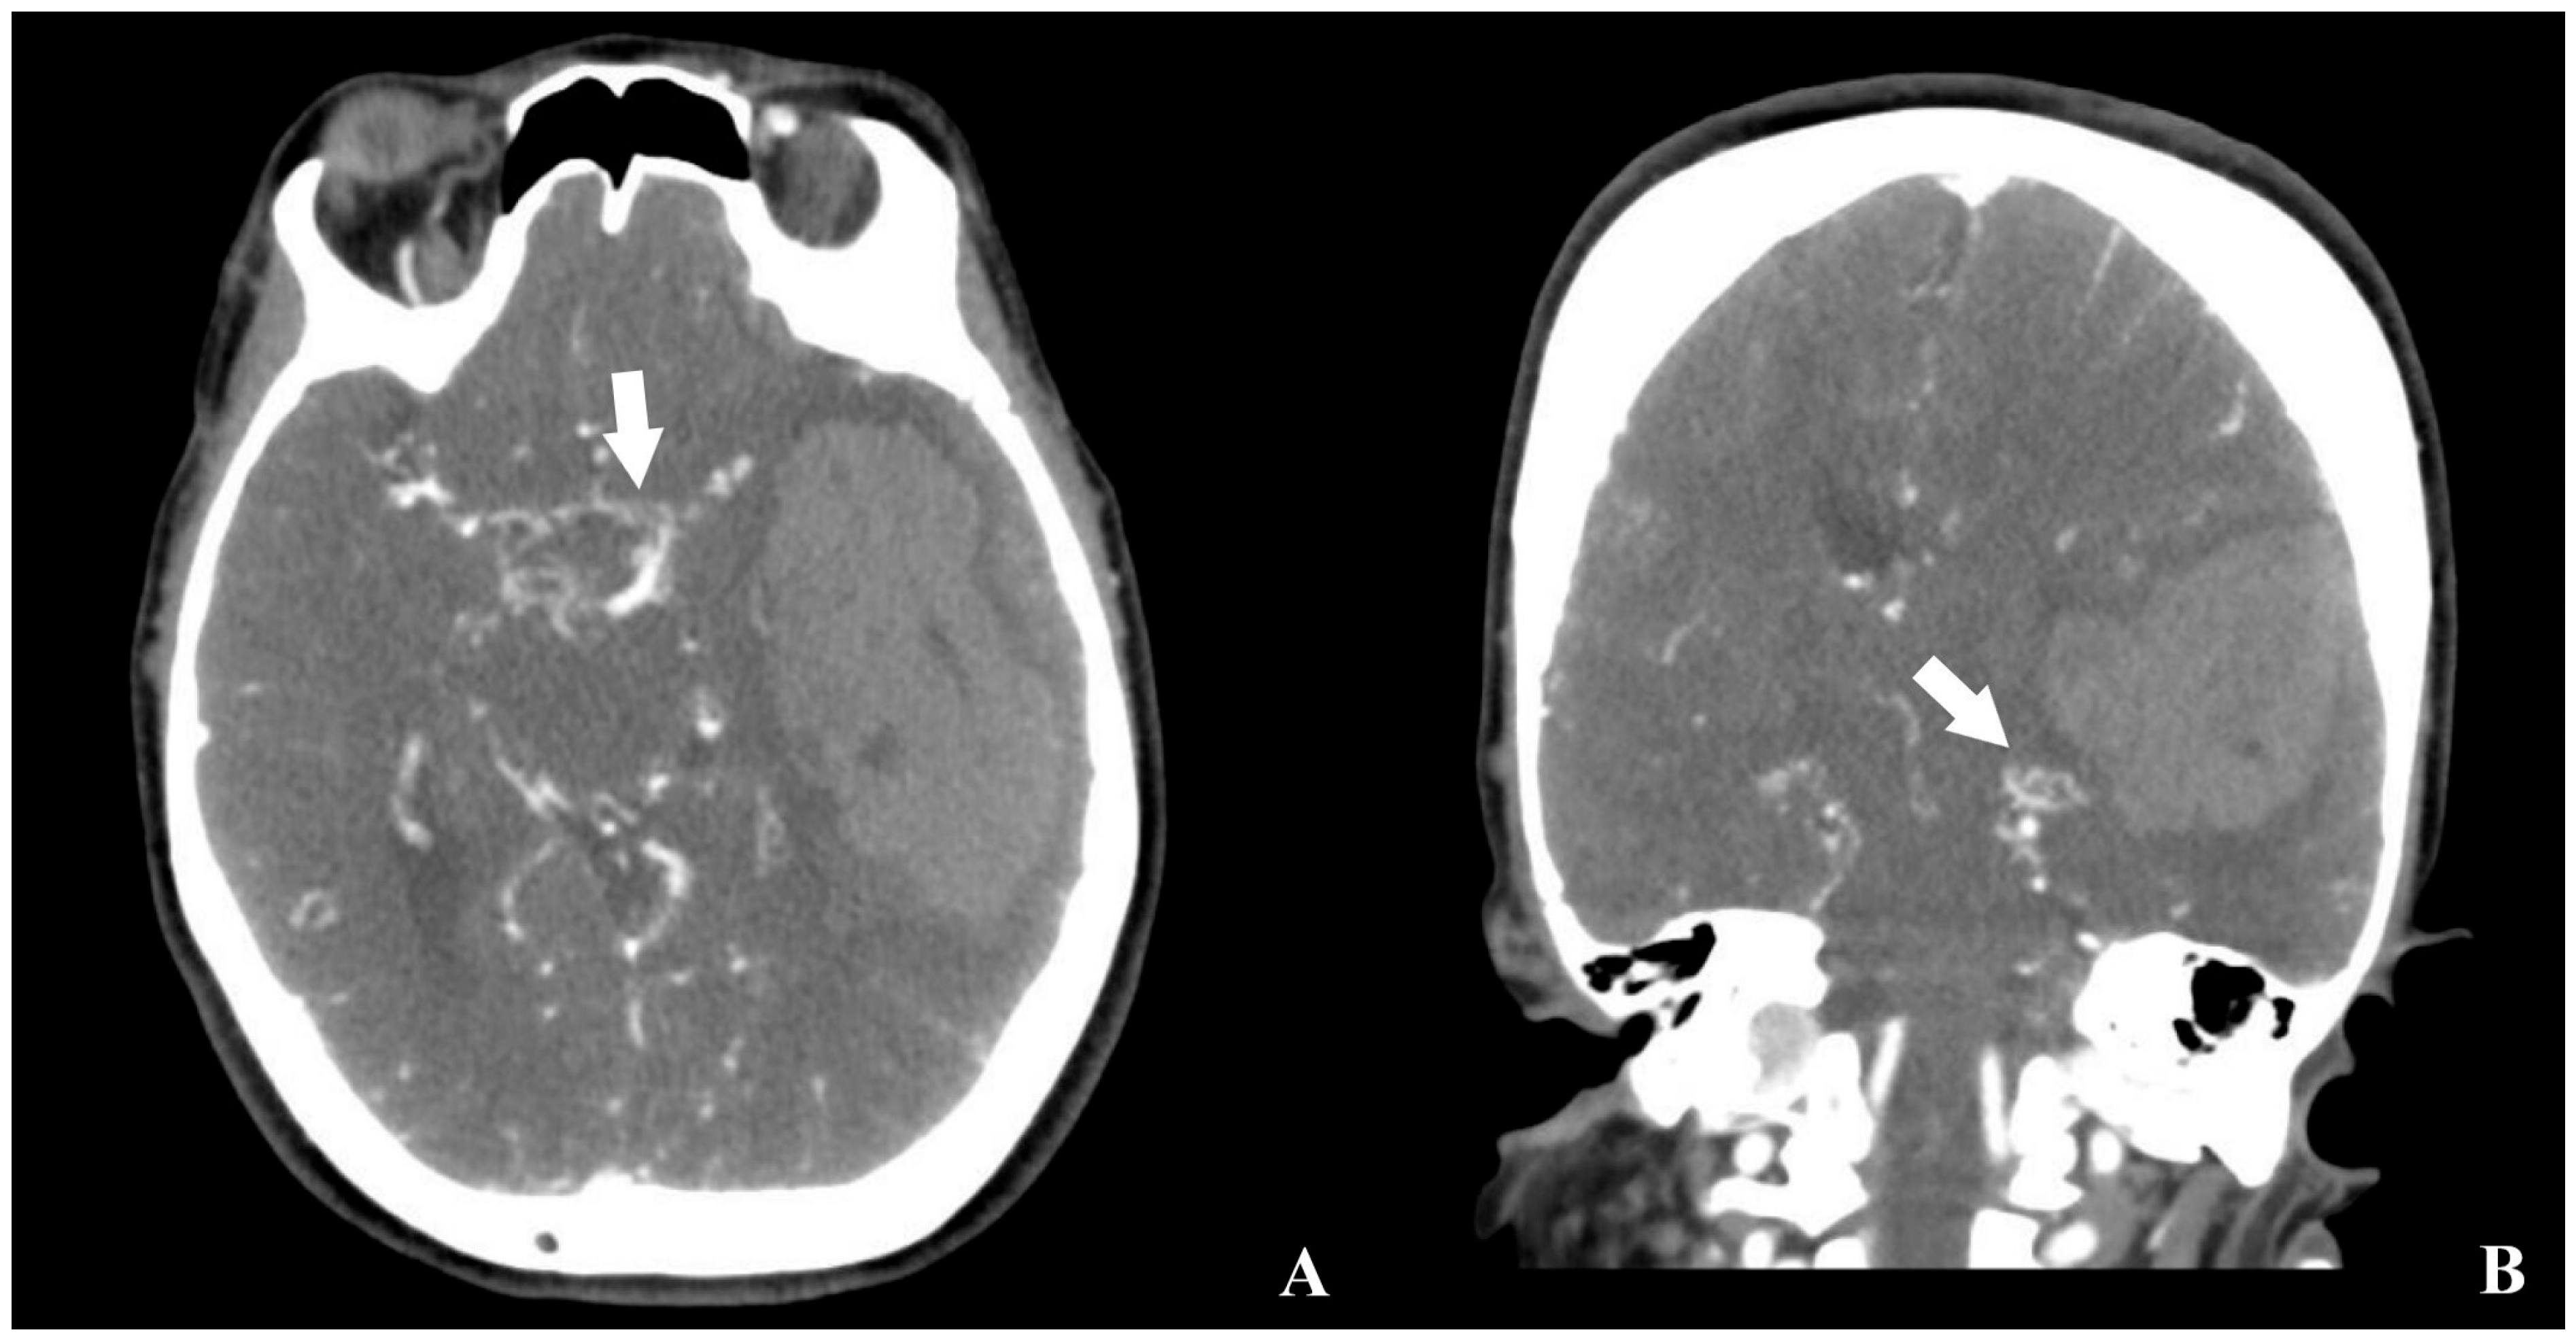

CT angiography revealed reduced calibers of the bilateral internal carotid arteries, along with prominent revascularization at the hematoma base and contralateral hemisphere. No aneurysms were identified (Figure 2).

Figure 2. Preoperative brain CTA of the patient ((A) axial, (B) coronal, white arrow: revascularized region adjacent to the hemorrhage).